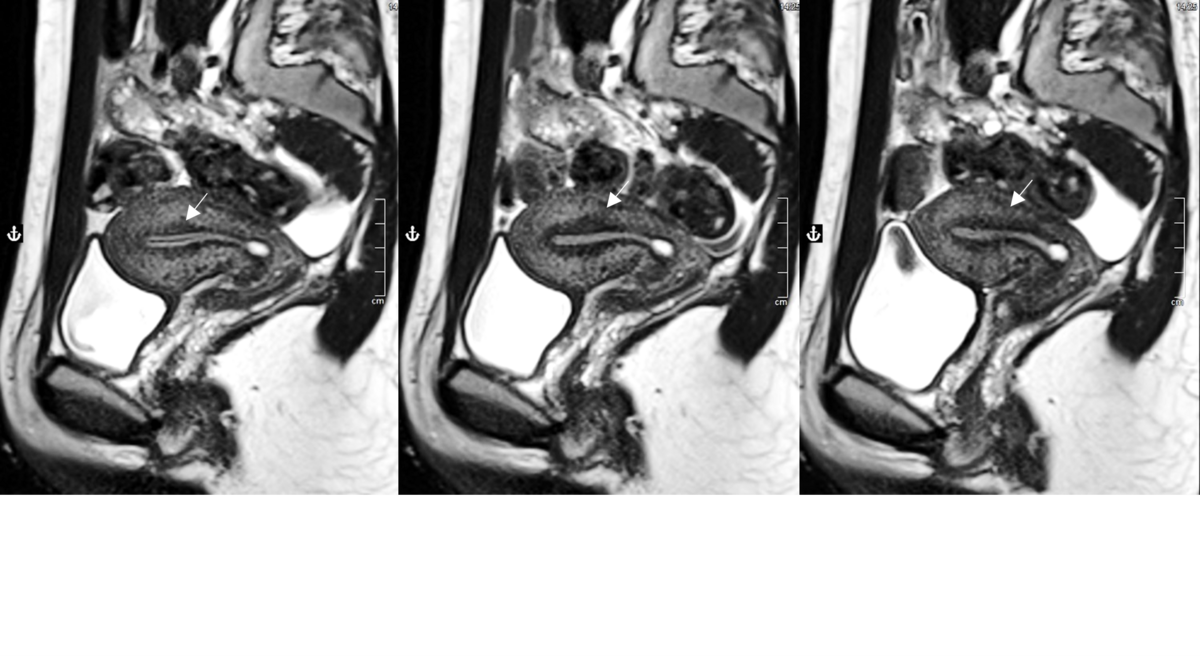

Anhand dieser manuellen und automatisierten Auswertungen liefert die Studie bereits neue Erkenntnisse zur junktionalen Zone als Biomarker. Überraschend zeigte sich, dass sich die Junktionalzone nicht nur zwischen den Untersuchungszeitpunkten, sondern auch während einer Untersuchung dynamisch verändert und somit vermutlich Muskelkontraktionen widerspiegelt. Es zeigte sich außerdem kein signifikanter Unterschied der Junktionalzonendicke zwischen symptomatischen und asymptomatischen Frauen zum selben Zykluszeitpunkt. Die Qualität der Junktionalzone als statisches Diagnosekriterium ist somit in Frage zu stellen. Die genannte Erkenntnis weist darauf hin, dass künftig der gesamte Uterus, insbesondere seine Peristaltik (Kontraktion) noch stärker in den Fokus der Forschung rücken muss. Wichtig dafür ist, den Untersuchungszeitpunkt mit dem weiblichen Zyklus abzustimmen.

Abbildung 1: T2w HASTE sagittal links initial im Vergleich zu den im Abstand von 10 min (mitte) und 17 min (rechts) aufgenommenen Wiederholungen der MRT-Sequenz. Erkennbar ist eine deutliche Variabilität der Morphologie und Dicke der Junktionalzone (JZ), sowie im rechten Bild eine Verdickung der Vorderwand. © Radiologisches Institut, Universitätsklinikum Erlangen